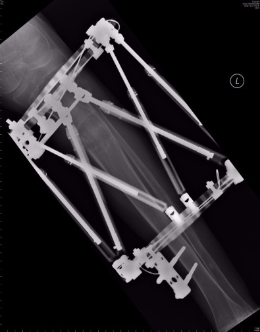

2. Lengthening of the shorter limb. The gradual and accurate limb lengthening cab be achieved with a circular external fixator (Taylor Spatial frame). The bone is surgically divided in theatre and gradual lengthening is performed using a circular external fixator, a process called distraction osteogenesis. This method addresses the short limb which is usually the limb with the problem and can also correct any deformities that may be present.

The x-ray below shows a patient’s tibia lengthening with the use of Taylor Spatial frame, by Dr. Zenios